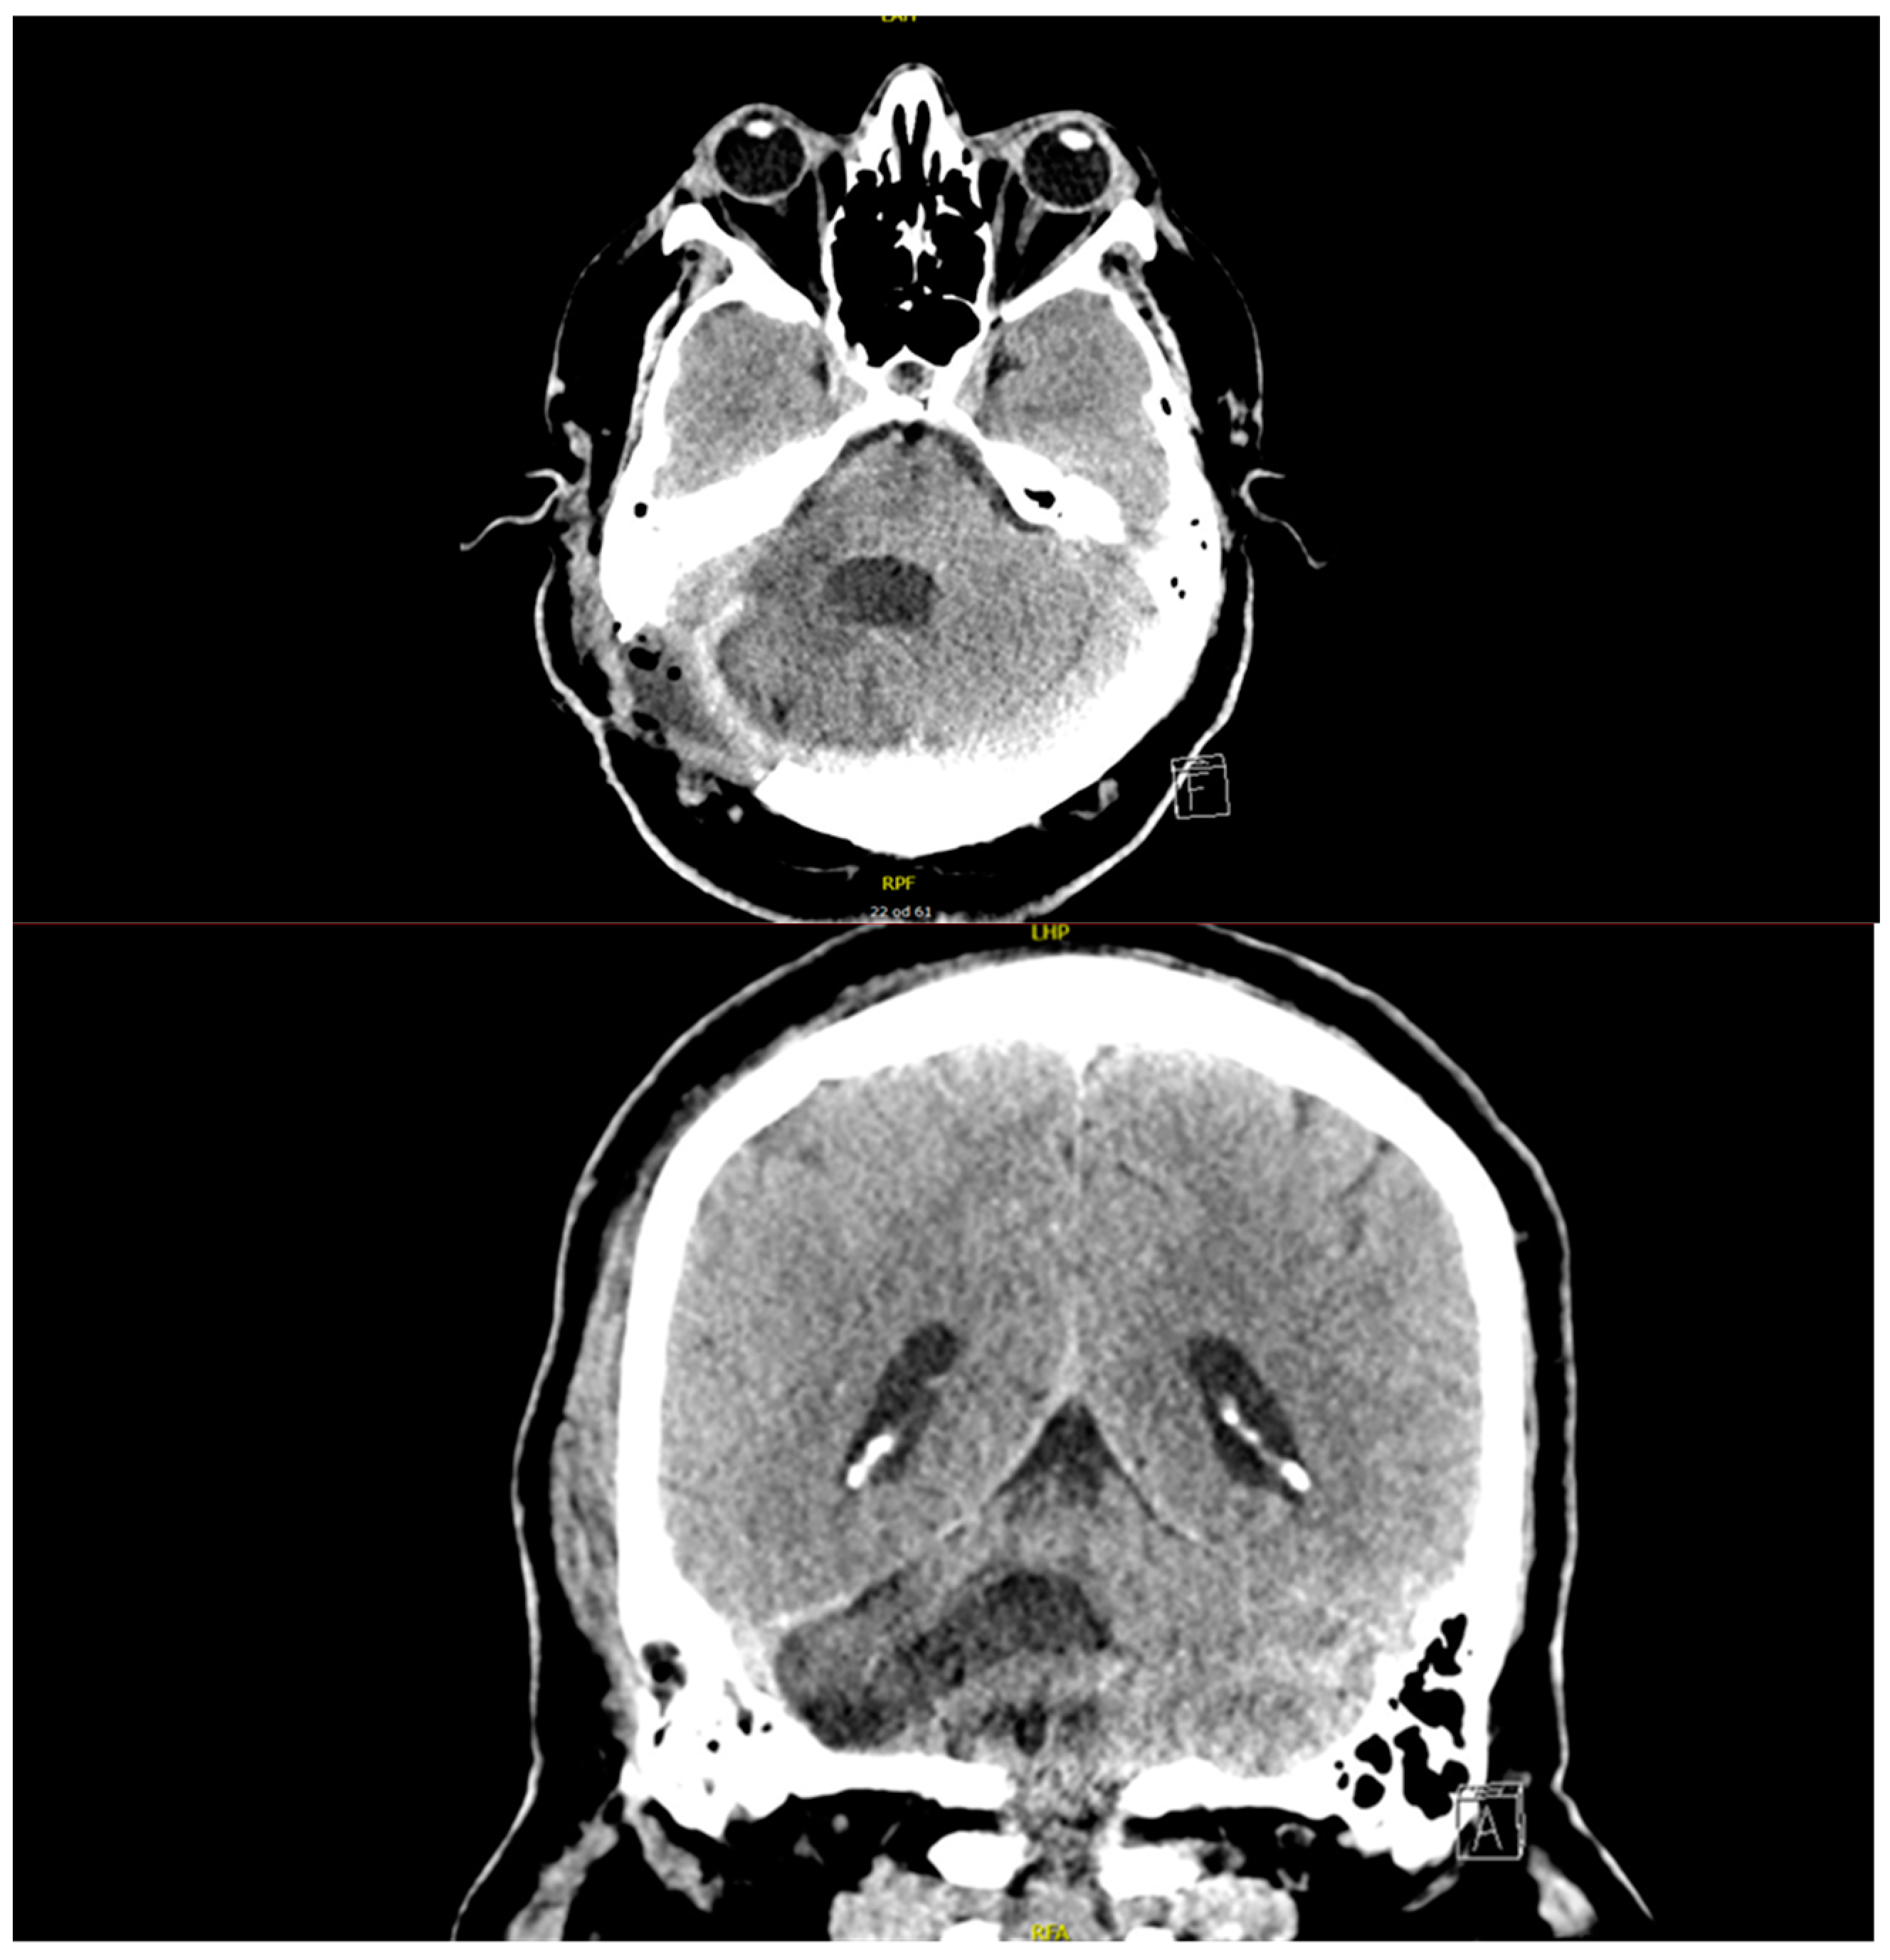

2.1. History and Diagnostic Process

2.2. Surgery

2.3. Postoperative Follow-Up and Complications